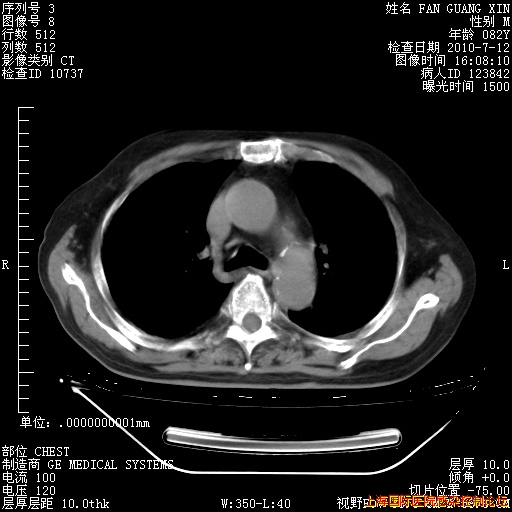

6月12日纵膈窗

回复